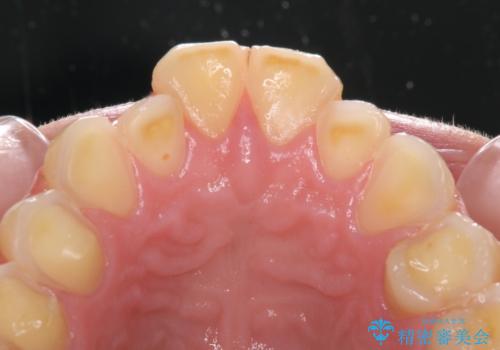

- 一時期の拒食症に伴い歯が酸で溶けてボロボロになってしまったとのことで来院された患者様です。

酸によりエナメル質の大半が溶けており、下顎前歯以外は酷いむし歯のような状態でした。

当初はほとんどの歯をむし歯治療のようにオールセラミッククラウンにて補綴治療を行う予定でしたが、仮歯に置き換えた時点で、口元の突出感や下顎前歯の叢生が気になるとのことで、上下左右の第一小臼歯4本を抜歯したワイヤー装置での抜歯矯正を行うこととしました。